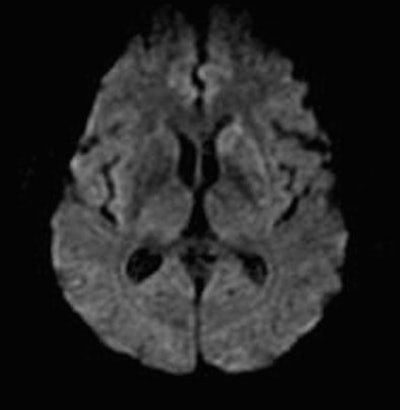

| Diffusion-weighted image as well as fluid-attenuated recovery T2-weighted images obtained two days after the initial perfusion CT and MRI demonstrate a hyperintense area close to that on the perfusion CBF and MTT maps and the initial diffusion-weighted imaging. A slight penumbra loss is demonstrated. Images courtesy of Dr. Sotirios Bisdas. |